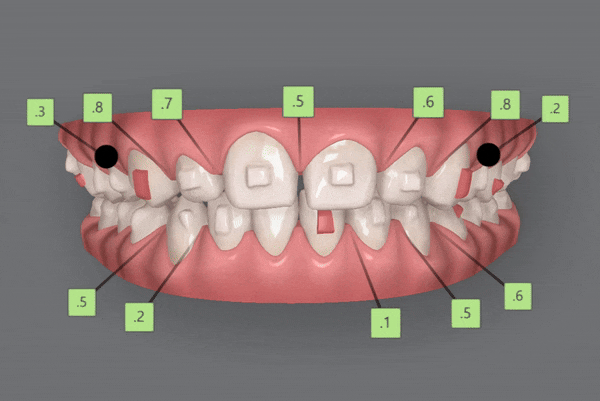

1st Clincheck

교정기간 23/7~24/6

잠실새내인비절라인 유펜바른치과의

첫번째 클린체크를 보시면

인비절라인라이트 케이스의

14개의 장치로 완성도 높은 치료 결과를

보여주었는데요^^

인비절라인 단 14개의 장치로

치아사이의 공간을 닫고

튀어나와있던 앞니의 각도를 개선시켜주었습니다~!